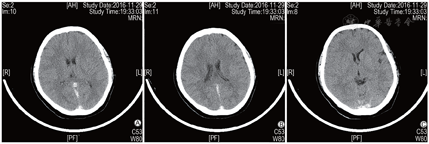

2016年8月1日患者行第1周期IVF-ET,采用黄体期短效长方案促排卵,促性腺激素(Gn)用药13 d、Gn总量2925 IU,扳机前一日雌二醇水平>11 010 pmol/L(本院检测值上限),取卵2枚,成胚1枚(6CII),因子宫内膜因素未行新鲜胚胎移植。2016年11月12日行第2周期IVF-ET,周期第2日卵泡刺激素(FSH)为4.87 IU/L,黄体生成素(LH)为6.84 IU/L,雌二醇为194 pmol/L,孕酮为3.21 nmol/L。采用短方案促排卵,皮下注射醋酸曲普瑞林(达必佳,德国辉凌制药)0.05 mg、肌内注射尿促性腺激素(hMG,珠海丽珠制药)150 IU+尿促卵泡素(丽申宝,珠海丽珠制药)150 IU启动。Gn第6日雌二醇水平>11 010 pmol/L,逐渐减少Gn用量。Gn持续使用11 d、Gn使用总量为2550 IU。周期第13日优势卵泡(直径>14 mm)达到扳机标准,B超示双侧卵巢明显增大,直径>14 mm卵泡20枚,稀释后查雌二醇水平为110 117 pmol/L,当晚肌内注射人绒毛膜促性腺激素(hCG,珠海丽珠制药)6000 IU。扳机后36 h行取卵术,获卵16枚,过程顺利。患者于取卵后12 h开始出现恶心、呕吐、腹胀,伴胸闷、憋气,尿量较前减少,体温正常,于取卵后当日晚间急诊就诊,急查白细胞计数(WBC)为21.34×109/L,红细胞比容(Hct)为55.30%,全血C反应蛋白(CRP)为16.59 mg/L,D-二聚体为670.00 μg/L,血钠水平为131.0 mmol/L,随机血糖(Glu)为14.48 mmol/L,妇科B超提示右侧卵巢大小约15.2 cm×12.2 cm×9.2 cm,左侧卵巢约13.8 cm×8.1 cm×6.8 cm,腹、盆腔内探及液性回声,较深处约4.1 cm,考虑重度OHSS。予以补液、抗凝等治疗,症状未见明显缓解。常规IVF授精,共获得4枚有效胚胎(3枚8CII、1枚7CII),冷冻保存。取卵术后第4日,患者突然出现肌力下降并跌倒,左侧肢体活动不灵,伴嗜睡,急症收入院。入院时血压120/91 mmHg,呼吸26次/min,心率120次/min,体温36.8 ℃,查体示瞳孔等大等圆,直径约3 mm,对光反射存在,双眼向右侧凝视,口角右歪,腹膨隆,左侧上下肢肌力为0级,右侧肌力5级,右侧肌张力正常。急查WBC为18.83×109/L,Hb为160 g/L,Hct为46.40%,D-二聚体为4 090.00 μg/L,纤维蛋白原(FIB)为4.86 g/L,CRP为12.42 mg/L,白蛋白为28.50 g/L,总胆固醇(TC)为7.25 mmol/L,甘油三酯(TG)为3.63 mmol/L,行颅脑CT提示矢状窦、直窦、双侧横窦、双侧乙状窦及额部部分静脉走行区密度不均匀增高X线计算机断层摄影(CT)值为70~80 Hu,考虑多发静脉窦和静脉走行区密度增高,血栓可能(图1),行颅脑磁共振静脉血管造影(MRV)提示双侧大脑大静脉-直窦、窦汇、双侧横窦显示不清,上矢状窦及其属支略扩张,考虑静脉血栓形成可能性大(图2)。入院诊断为“肌力下降原因待诊:颅内血栓形成?、OHSS(重度)、Ⅱ型糖尿病、高血压病、高脂血症、低蛋白血症、乙肝小三阳、原发性不孕症、IVF术后(2次)”。入院后立即给予甘露醇(天津百特医疗)降颅压及低分子肝素抗凝治疗,并在局部麻醉下行经股动脉插管全脑动脉造影术+全脑血管造影+静脉窦球囊扩张+溶栓及取栓术。手术顺利。术后造影提示静脉窦较前明显通畅,上矢状窦、横窦及乙状窦均显影,脑血管回流较术前明显改善。术后继续予以补液、抗凝、降颅压、改善脑循环等对症治疗。患者恢复好,复查血WBC、D-二聚体、Hct、雌二醇水平逐渐恢复正常,于2周后顺利出院。出院后继续予以低分子肝素钠注射液(法安明,美国辉瑞药业)5000 IU皮下注射 qd抗凝治疗,定期复查,未见明显异常。

A示矢状窦; B示直窦; C示乙状窦、横窦